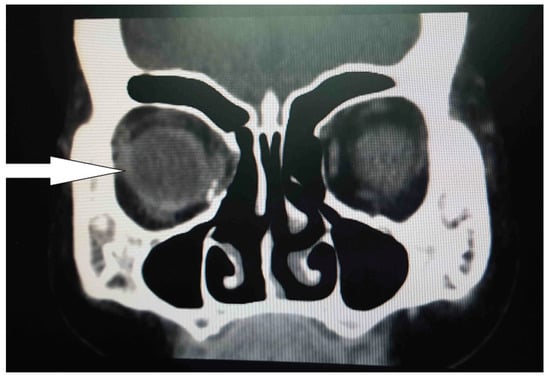

Diagnostic Assessment